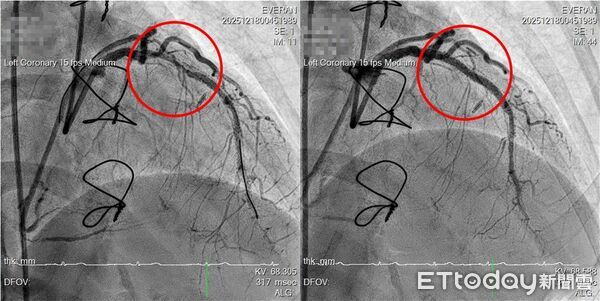

▲▼長安醫院利用震波碎石術,解決患者血管繞道術後心臟仍缺血之苦。(圖/長安醫院提供)

台中市1名57歲的李小姐長期罹患冠狀動脈疾病,曾在醫學中心接受心導管治療並放置藥物塗層支架,後續又再接受冠狀動脈繞道手術。然而術後胸悶與放射性背痛症狀仍反覆出現,病情加劇,經長安醫院心血管中心主任盧炯睿以「IVL血管內震波碎石術」震碎鈣化組織, 這才終結困擾多年的「心頭之患」。

盧炯睿指出,患者多次介入治療後仍反覆狹窄,且合併嚴重鈣化的支架內再狹窄病灶,若僅使用傳統高壓球囊,容易出現擴張不足,甚至增加血管剝離或破裂的風險,在評估各種條件後,決定導入「IVL血管內震波碎石術」。

該技術透過低能量、精準控制的震波作用,破壞深層鈣化結構,使血管恢復順應性,進而協助後續支架的擴張與置放。IVL的概念可比喻為「處理老舊水管內頑固水垢」,不同於單純以高壓球囊硬撐,IVL著重於改變鈣化結構本身,以降低血管損傷風險並提升治療效果。但該技術並非適用於所有病人,仍需依個別病灶條件審慎評估。